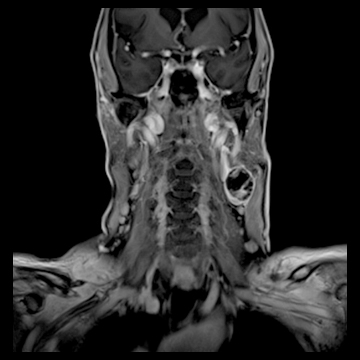

頚部腫瘍

- 造影3D VIBE

- 体動の影響を受けにくい